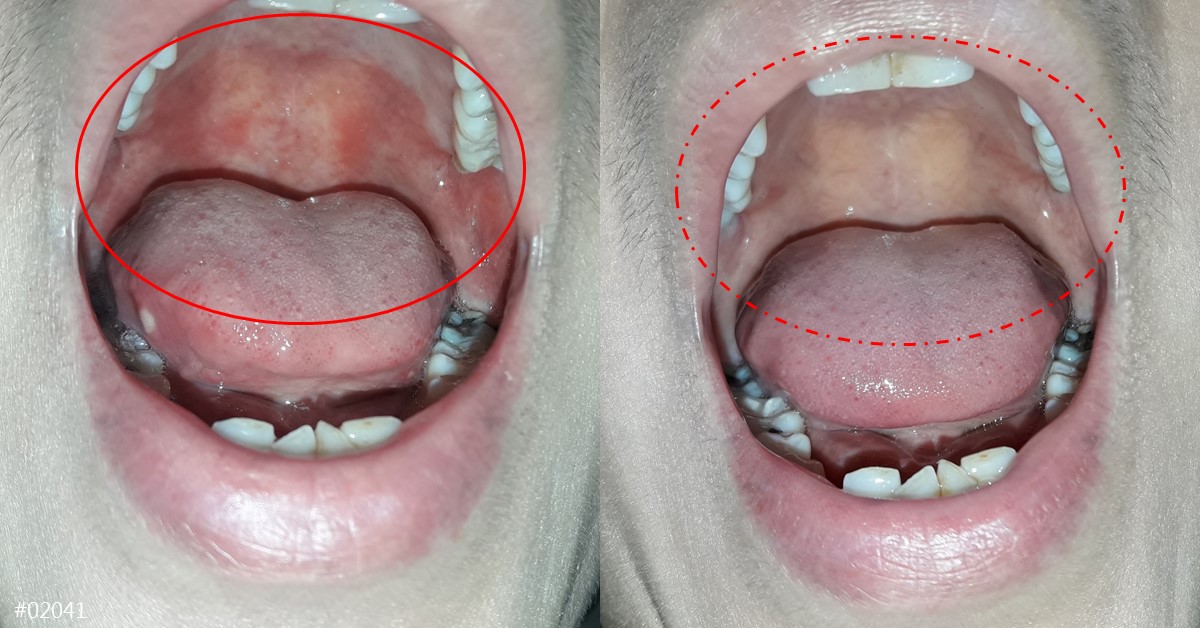

嘴破舌破(口腔潰瘍)治療案例

女病友,30 歲。因為照顧小孩晚上無法好好睡覺,導致抵抗力下降火氣大,喉嚨跟舌頭整個口腔破很多洞。